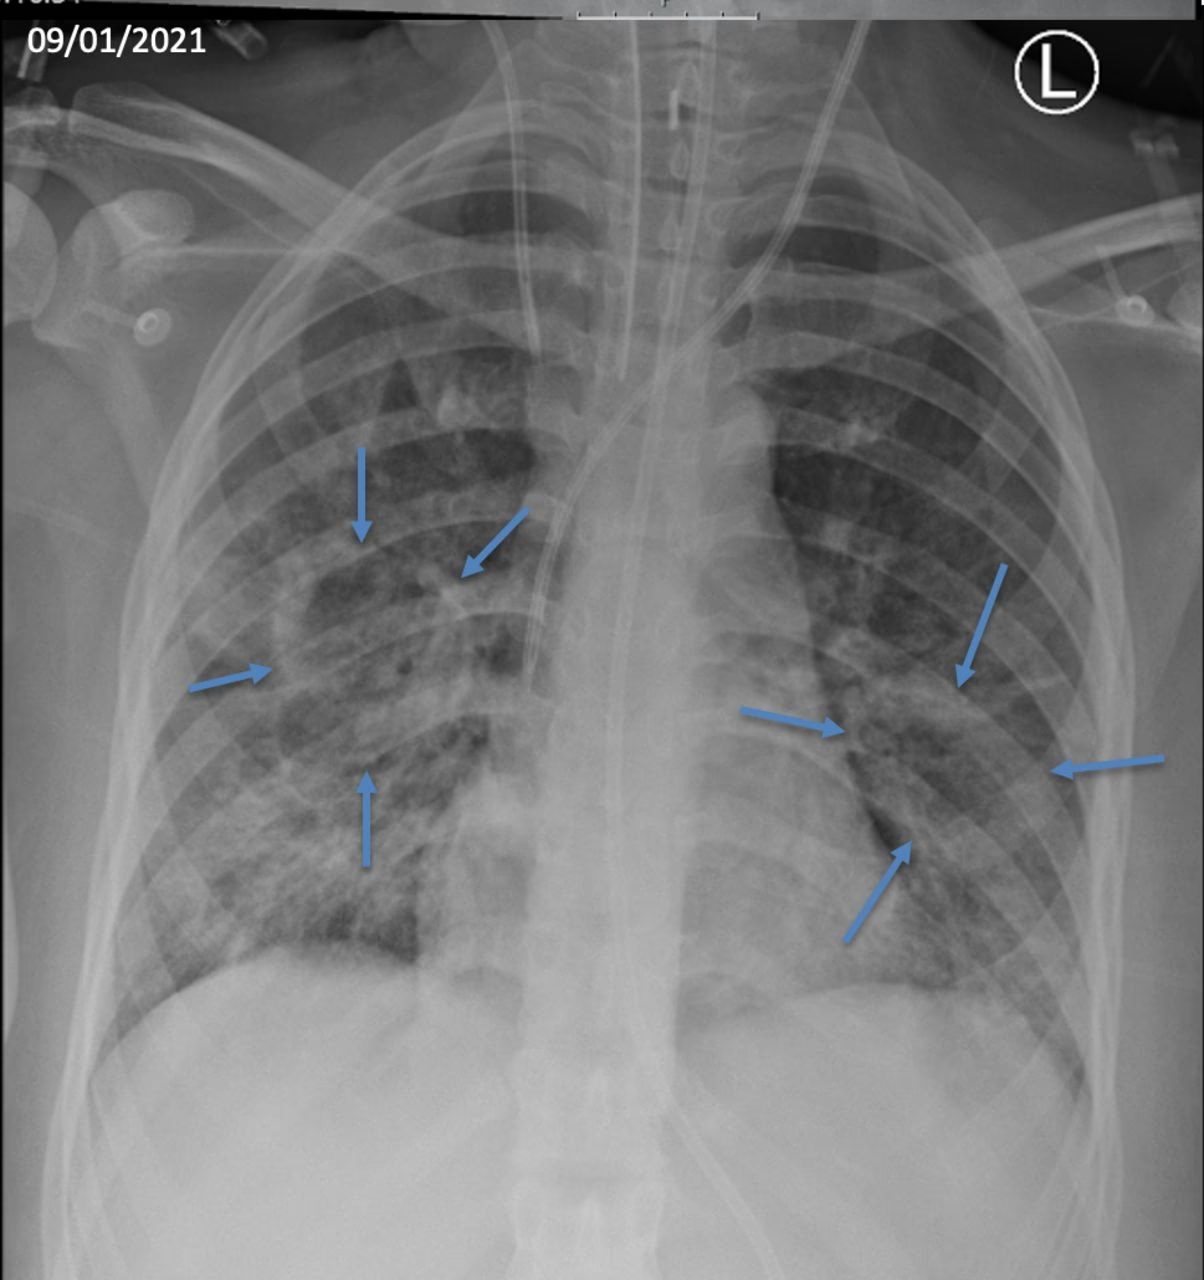

Tidligt i sygdomsforløbet viser røntgenbilleder typisk tegn på bronkopneumoni. Infiltratet (fortætningen) i lungen kan være plettet og begrænset, eller det kan være tæt, homogent og involvere en hel lungelap eller endda en hel lungehalvdel. Hos omkring halvdelen af de ramte patienter ses sygdom i begge lunger.

Det mest sigende diagnostiske tegn er den ekstremt hurtige udvikling. Et sygdomsbillede, der på få timer udvikler sig fra en simpel lungebetændelse til empyem (pusansamling i pleurahulen) eller pyopneumothorax, med eller uden dannelse af pneumatoceler (tyndvæggede, luftfyldte cyster i lungen), peger meget kraftigt i retning af en stafylokokinfektion. Selvom intet røntgenbillede er 100% diagnostisk, er denne hurtige forværring et afgørende klinisk fingerpeg.